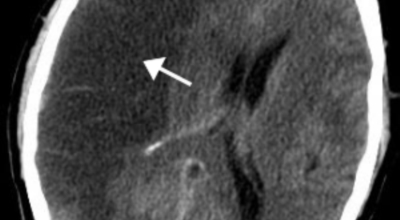

뇌졸중은 뇌경색과 뇌출혈 두가지로 나뉘게 됩니다. 먼저 뇌경색은 뇌혈관이 막혀 영양분과 산소를 주는 피가 통하지 않는 상태로 원은은 크게 세 가지로 나눌 수 있는데요 동맥경화증이 생겨 좁아진 부위로 인해서 혈액공급이 부족해지거나 좁아지다가 결국 막혀버리는 경우, 큰 혈관에서 분지한 작은 혈관들이 고혈압 등으로 압박을 받으면 혈관이 막히는 경우가 있어요.

또한 심장 판막질환이나 심방세동 또는 심근병 등의 심장 질환이 있는 경우 심장에서 혈전이 만들어지고 그게 뇌로 흘러가게 되면 뇌혈관을 막게 되는 경우가 있습니다. 뇌출혈은 뇌경색과 반대로 뇌혈관이 터져서 발생하는 뇌내 출혈과 거미막하 출혈로 나누게 되어요. 거미막하출혈은 혈관벽의 약한 부분이 부풀어 오르는 뇌동맥류가 터지는 경우와 연관성이 크다고 합니다.

뇌졸중 후유증

뇌졸중이 치명적인 이유는 한 번 손상된 뇌 조직은 다시 좋아지지 않기 때문이죠. 뇌졸중은 발생 후 시간이 지날수록 점점 진행되므로 빠른 치료가 생명인데요 시간이 지나면서 손상된 부분의 기능을 다른 정상적인 조직이 도움 줌으로써 증상이 개선될 수는 있으나 치료 시기가 늦을수록 치료 효과는 줄이고 부작용이 더 커지며 후유증이 크게 남을 수 있습니다.

초기 뇌경색이 진행하거나 재발할 수 있기 때문에 뇌졸중 진행을 막기 위해서 빨리 내원해서 치료해야 한다는 점이 중요합니다. 급성 뇌졸중 치료가 종료된 이후 뇌졸중 환자들은 여러 부분 어느 정도의 장애를 갖게 되는데 적극적이고 빠른 재활치료를 통해 육체 기능이 호전되는 것이 가능합니다.

뇌세포는 몇 분만 혈액공급이 안 되어도 손상을 입게되고 한 번 죽은 뇌 세포는 다시 살릴 수 없게 되어 빠른 치료가 중요시되는 질병입니다. 뇌세포가 손상되는 시간은 발병 후에 3시간에서 최대 6시간이면 손을 쓸 수 없이 손상을 받기 때문에 뇌졸중을 담당하는 의사들은 뇌졸중의 골든타임을 발병 3시간에서 6시간 이내로 보고 있다고 하네요. 그렇기 때문에 발견 즉시 병원으로 가서 치료를 받으시는 것이 중요하다는 점 기억하세요.